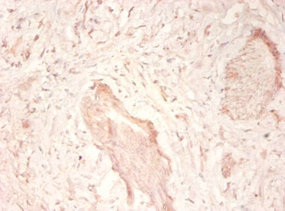

Immunohistochemistry of paraffin-embedded human prostate tissue using CSB-PA11509A0Rb at dilution of 1:50